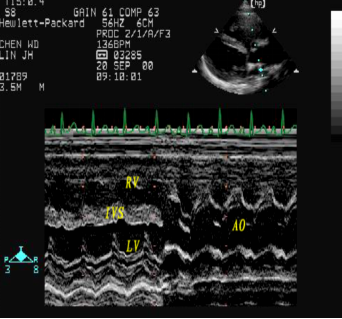

法洛四联症:超声心动图表现

室间隔缺损、主动脉骑跨

右室流出道狭窄

连续波多普勒测量右室流出道压差